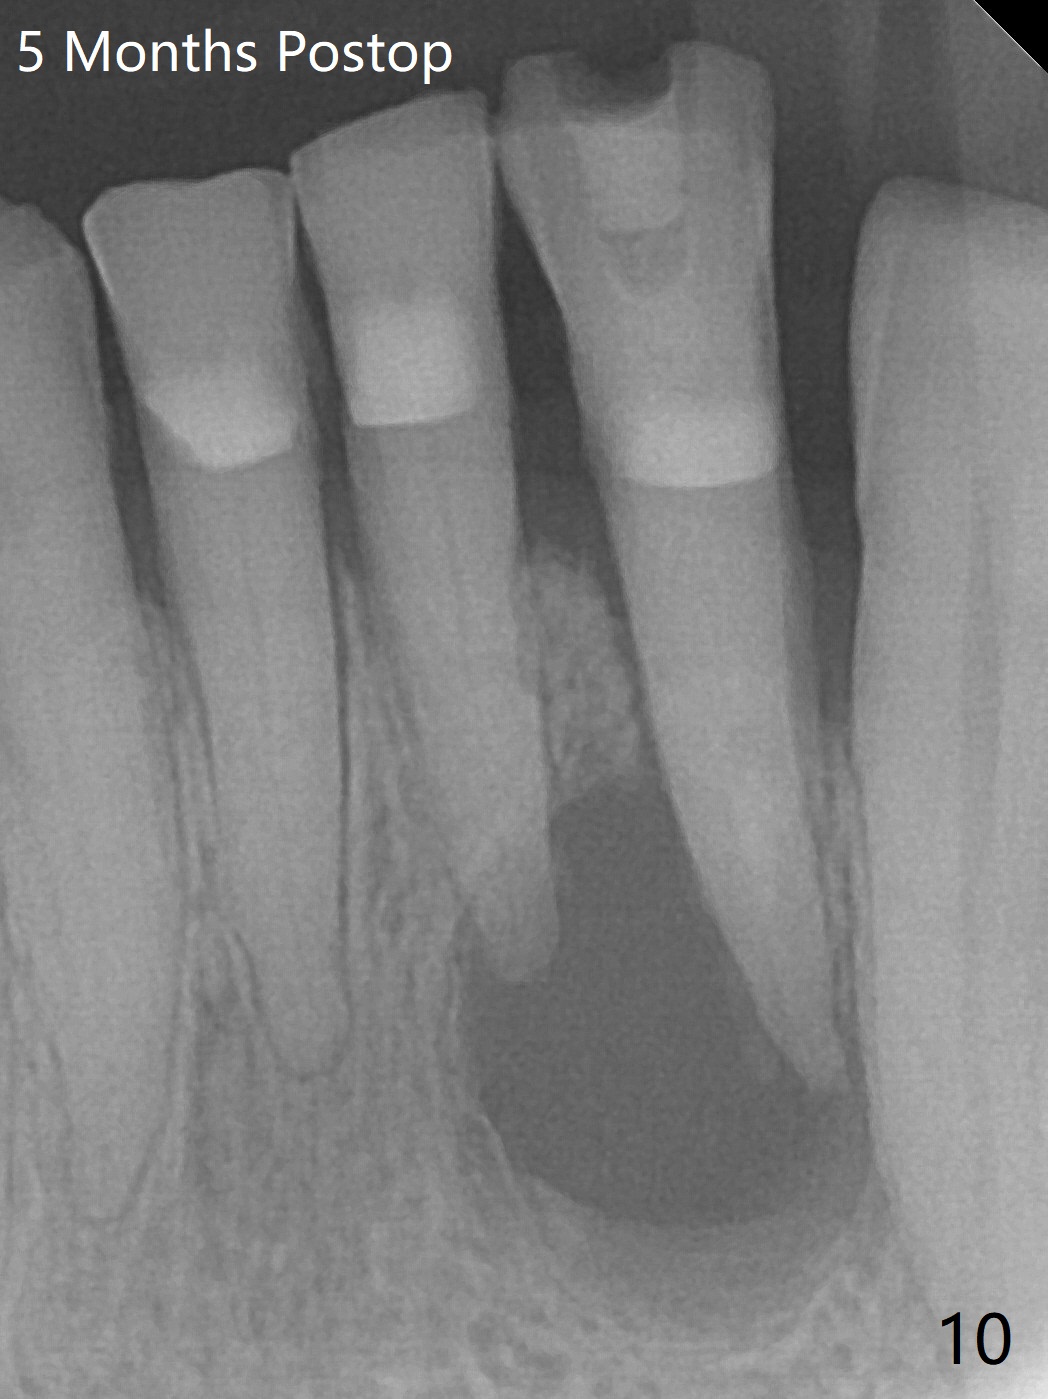

A 73-year-old woman has discomfort associated with #23 four months post Class V composite at #23-25 (Fig.1 C (*: Class V lesions)). Bone loss seems to be more severe lingually, especially at the crest (Fig.2 L). It appears that the apex of the tooth #24 is also in the large apical lesion (Fig.3). Class V composite is apparently continuous with the pulp at #25,24,23 (Fig.5-7). In contrast, Class V defect does not involve the pulp at #26 (Fig.4). If necrosis is confirmed clinically for #23 24 and 25, RCT will be conducted. Due to 7-day Amoxicillin taken for #3 implant, the patient feels that her tongue moves freely, as related to reduction in pain and swelling lingual to #23 (Fig.8 *). Endo ice test shows necrosis of #23 to 25. RCT is initiated at #23 (Fig.9) with buccal and lingual swelling. Endo may have to be at #24 with apicoectomy with PRF. The lingual swelling remains at #23, although there is no pain or purulent discharge 5 and 5.5 months post debridement (Fig.10,11). RCT is finished (Fig.12). Apicoectomy is pending with PRF. Less aggressive curettage will be done at #24 to maintain apical blood supply. Vitality tests have been done without conclusion.